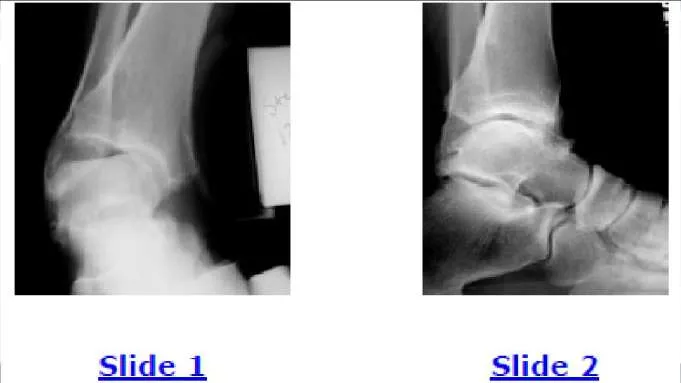

Question 8:

A 43-year-old patient presents for treatment of a chronically painful ankle. He notes pain with ambulation, is unable to exercise, and has had marked swelling of the ankle for the last 6 months. When walking, he notes continued instability of the ankle. Examination of the ankle is unremarkable with the exception of swelling. A plain radiograph and intraoperative photograph are shown (Slide 1 and Slide 2). The most likely cause for this condition is:

Correct Answer: Pigmented villonodular synovitis

Explanation:

The appearance of the synovium is typical of pigmented villonodular synovitis. Staining of the synovium is characteristic. It is unlikely that a 43- year-old man will present with rheumatoid arthritis, although synovitis may appear similar. Recurrent ankle sprains cause a nonspecific synovitis that is not pigmented.